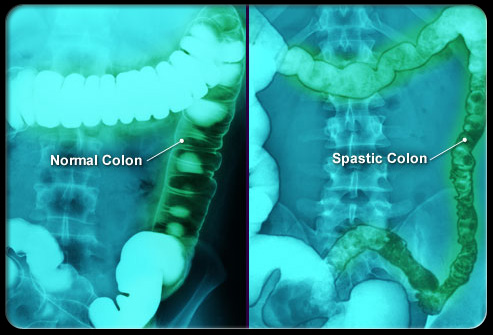

肠易激惹综合征 (IBS)

盆腔和腹部疼痛、胀气、时不时出现的便秘或腹泻通常是肠易激惹综合征(IBS)造成的。IBS是一种伴有反复发作症状的慢性功能性疾病。IBS的治疗包括调整饮食、管理压力和用药。